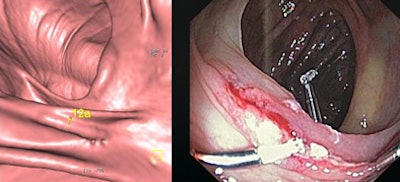

![]() |

| Above, CAD missed a large rectal mass. Below, CAD missed a 3-cm flat tubulovillous adenoma that was also missed by the radiologist. |

"It was a flat tubular adenoma that I actually missed and so did CAD," Graser said. "It looks like a fold in the endoluminal view, and you see the fold in 2D as well. Its texture is different from this adjacent fold, and this was why the endoscopist did detect it and it was resected."